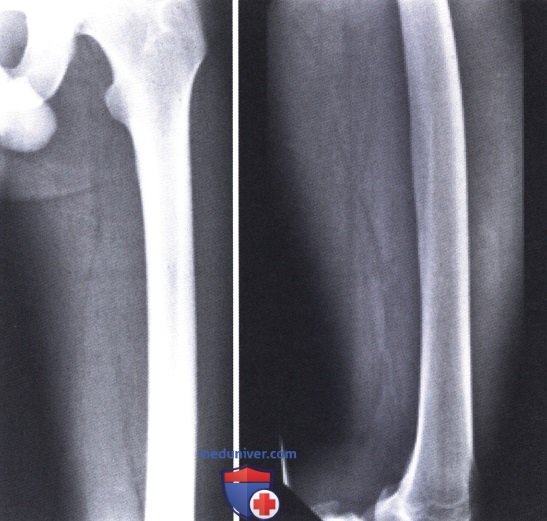

Оссификация тазобедренных суставов: что это и как проявляется?